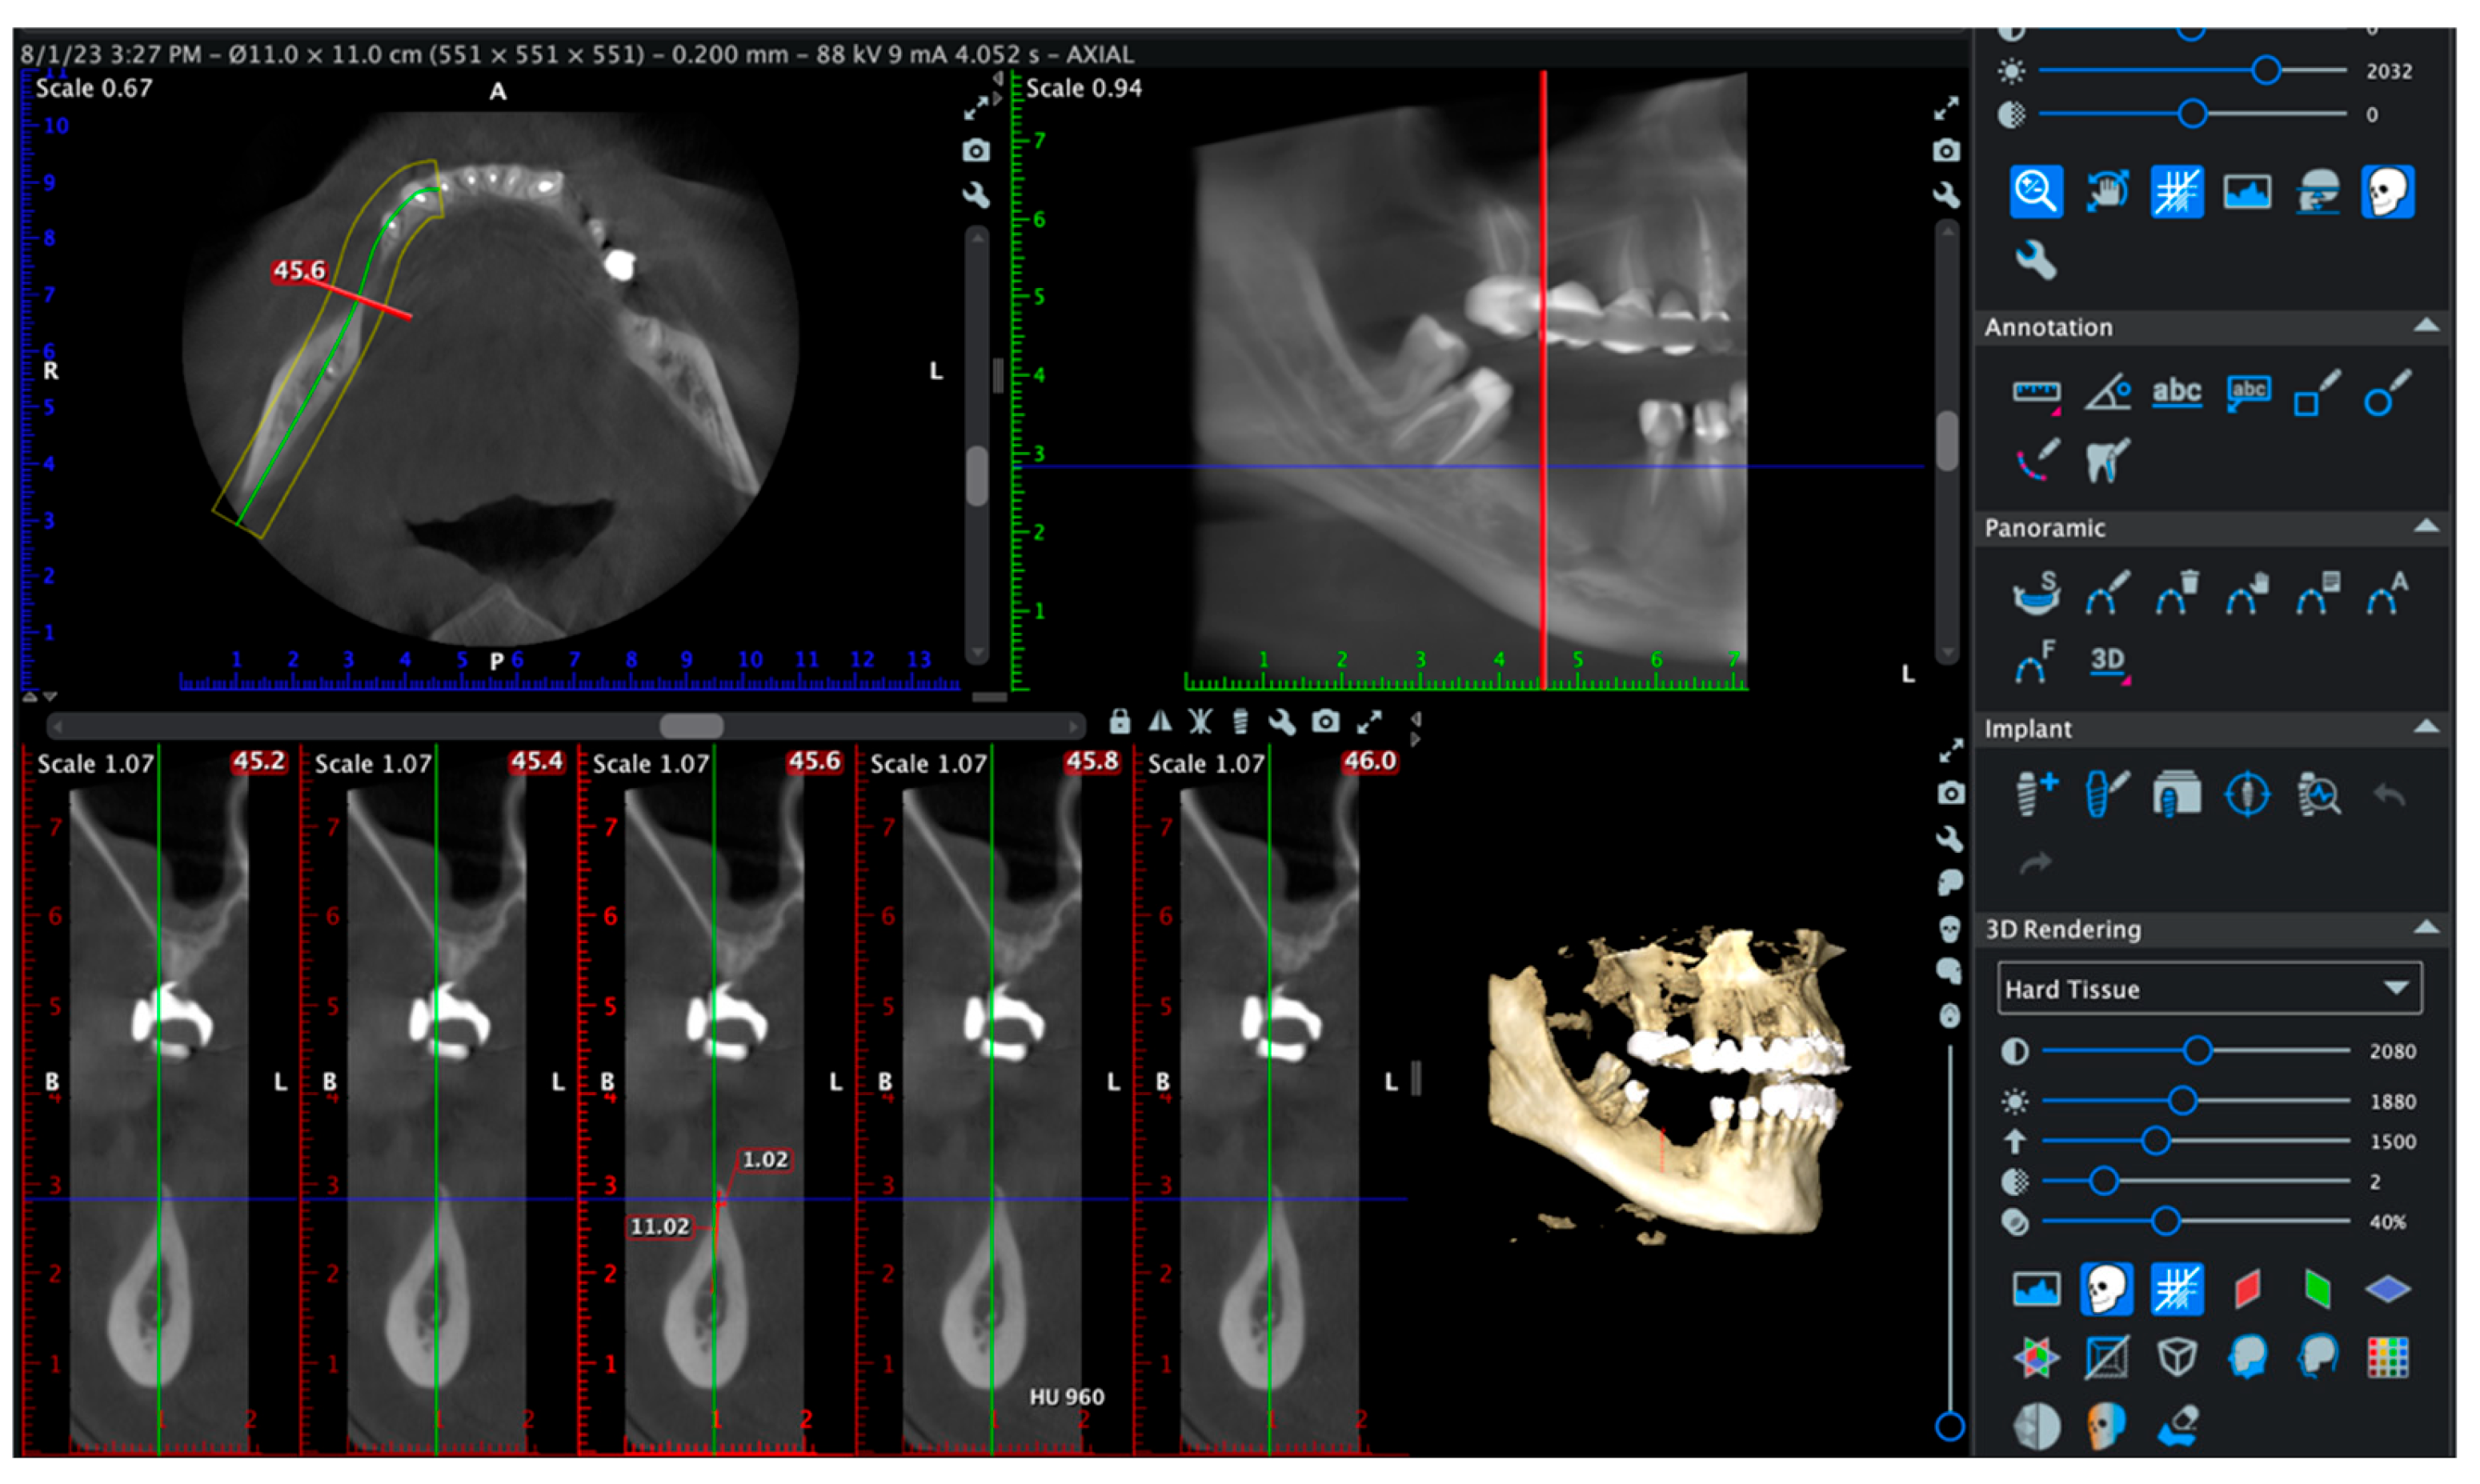

A representative case is shown in Figure 6 to illustrate the CBCT-based evaluation protocol. Cross-sectional slices between 45.2 and 46.0 mm were analyzed using the same acquisition settings and patient positioning as in all other cases. Radiographic measurements were performed by a calibrated examiner using standardized tools. This example demonstrates the methodology used to assess ridge width, trabecular density, and cortical continuity.

All scans were acquired with identical device settings and patient positioning, and all radiographic measurements were performed by a calibrated examiner as seen in Figure 7.

Figure 7. CBCT-based evaluation at 6 months postoperatively in a representative case. Cross-sectional analysis at 45.6 mm revealed a horizontal ridge width of 11.02 mm and a trabecular bone density estimated at 960 Hounsfield Units (HU). The buccal and lingual cortices were intact, with no evidence of dehiscence or fenestration. The 3D volumetric reconstruction confirmed complete bone coverage and spatial integrity around the radiopaque implant structure.